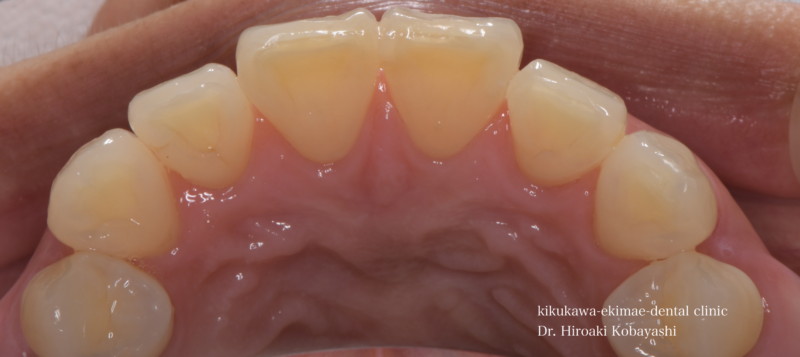

歯並びを気にされて来院されました。見た目改善を目的にワイヤーによる部分矯正を希望されました。 ブラケット装着用のマウスピースを作り、ブラケット装着を行います。   弱い力をかけながら、ワイヤーにより歯を動かします。強い力を急にかけると歯の根が吸収されてしまいます。なので弱い力で歯を動かすことによって根への負担が少なく歯根吸収のリスクが少なくなります。               6ヶ月程度で歯の並びを改善することができました。   before after